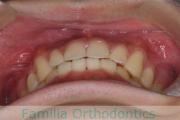

上顎

下顎

前歯の関係など